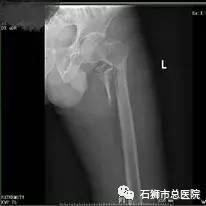

股骨骨折

股骨粗隆间粉碎性骨折

手术 · 前